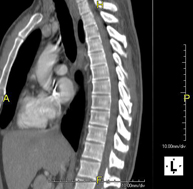

- TC Columna Dorsal

Prueba radiológica que consiste en obtener imágenes de las vértebras dorsales de alta definición anatómica mediante el empleo de un equipo de TC (Tomografía Computarizada). Indicaciones: dolor dorsal agudo/crónico, traumatismo, columna desviada.

Prueba radiológica que consiste en obtener imágenes de las vértebras dorsales de alta definición anatómica mediante el empleo de un equipo de TC (Tomografía Computarizada). Indicaciones: dolor dorsal, estudio de desviaciones de la columna, traumatismo.

- TC Columna lumbar

Prueba radiológica que consiste en obtener imágenes de las vértebras lumbares de alta definición anatómica mediante el empleo de un equipo de TC (Tomografía Computarizada). Indicaciones: dolor lumbar sin/con irradiación a piernas, dificultad para caminar, traumatismo.